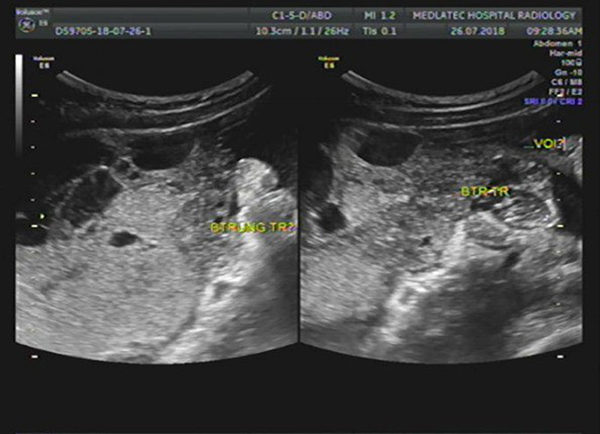

Thực tế siêu âm buồng trứng là một trong những phương pháp sử dụng đầu dò có phát sóng siêu âm để đưa sâu vào âm đạo. Phương pháp này còn được nhiều người gọi với tên khác là siêu âm đầu dò âm đạo. Thông qua kỹ thuật chuyên sâu này, bác sĩ có thể đưa ra đánh giá chính xác về tình trạng của buồng trứng, tử cung và nhiều vùng khác. Bởi phương pháp siêu âm đầu dò buồng trứng mang đến kết quả chẩn đoán chính xác khá cao.

Bên cạnh việc sử dụng sóng siêu âm ở đầu dò để khám buồng trứng, tử cung, phương pháp này còn được áp dụng với nhiều kỹ thuật khác để siêu âm ổ bụng. Với cách siêu âm này, kích thước cũng như tình trạng của buồng trứng sẽ được khám và cho ra kết quả chính xác nhất.

Nhờ áp dụng phương pháp này mà bác sĩ sẽ có thể đưa ra chẩn đoán cũng như kịp thời đánh giá tình trạng của buồng trứng. Nếu nhận thấy sự bất thường của buồng trứng, tử cung như xuất hiện khối u, bác sĩ sẽ kịp thời can thiệp để hạn chế những ảnh hưởng mà người bệnh có thể gặp phải. Vì thế mà quá trình điều trị cũng diễn ra suôn sẻ và đạt hiệu quả cao hơn.

– Giúp quan sát được kích thước của buồng trứng để kiểm tra sức khỏe sinh sản, chẩn đoán nữ giới có mang thai hay không,…

– Giúp theo dõi được quá trình phát triển của buồng trứng, độ dày niêm mạc,…

– Thông qua phương pháp này, bác sĩ có thể nhận định được nữ giới có mang thai ngoài dạ con hay không.

Ngoài ra, siêu âm đầu dò buồng trứng chỉ có thể cho ra các hình ảnh ở tiểu khu như tử cung, buồng trứng,… mà không thể xem hết được các tạng ở phía trên ổ bụng. Do đó, gây ra khá nhiều khó khăn khi thăm khám.